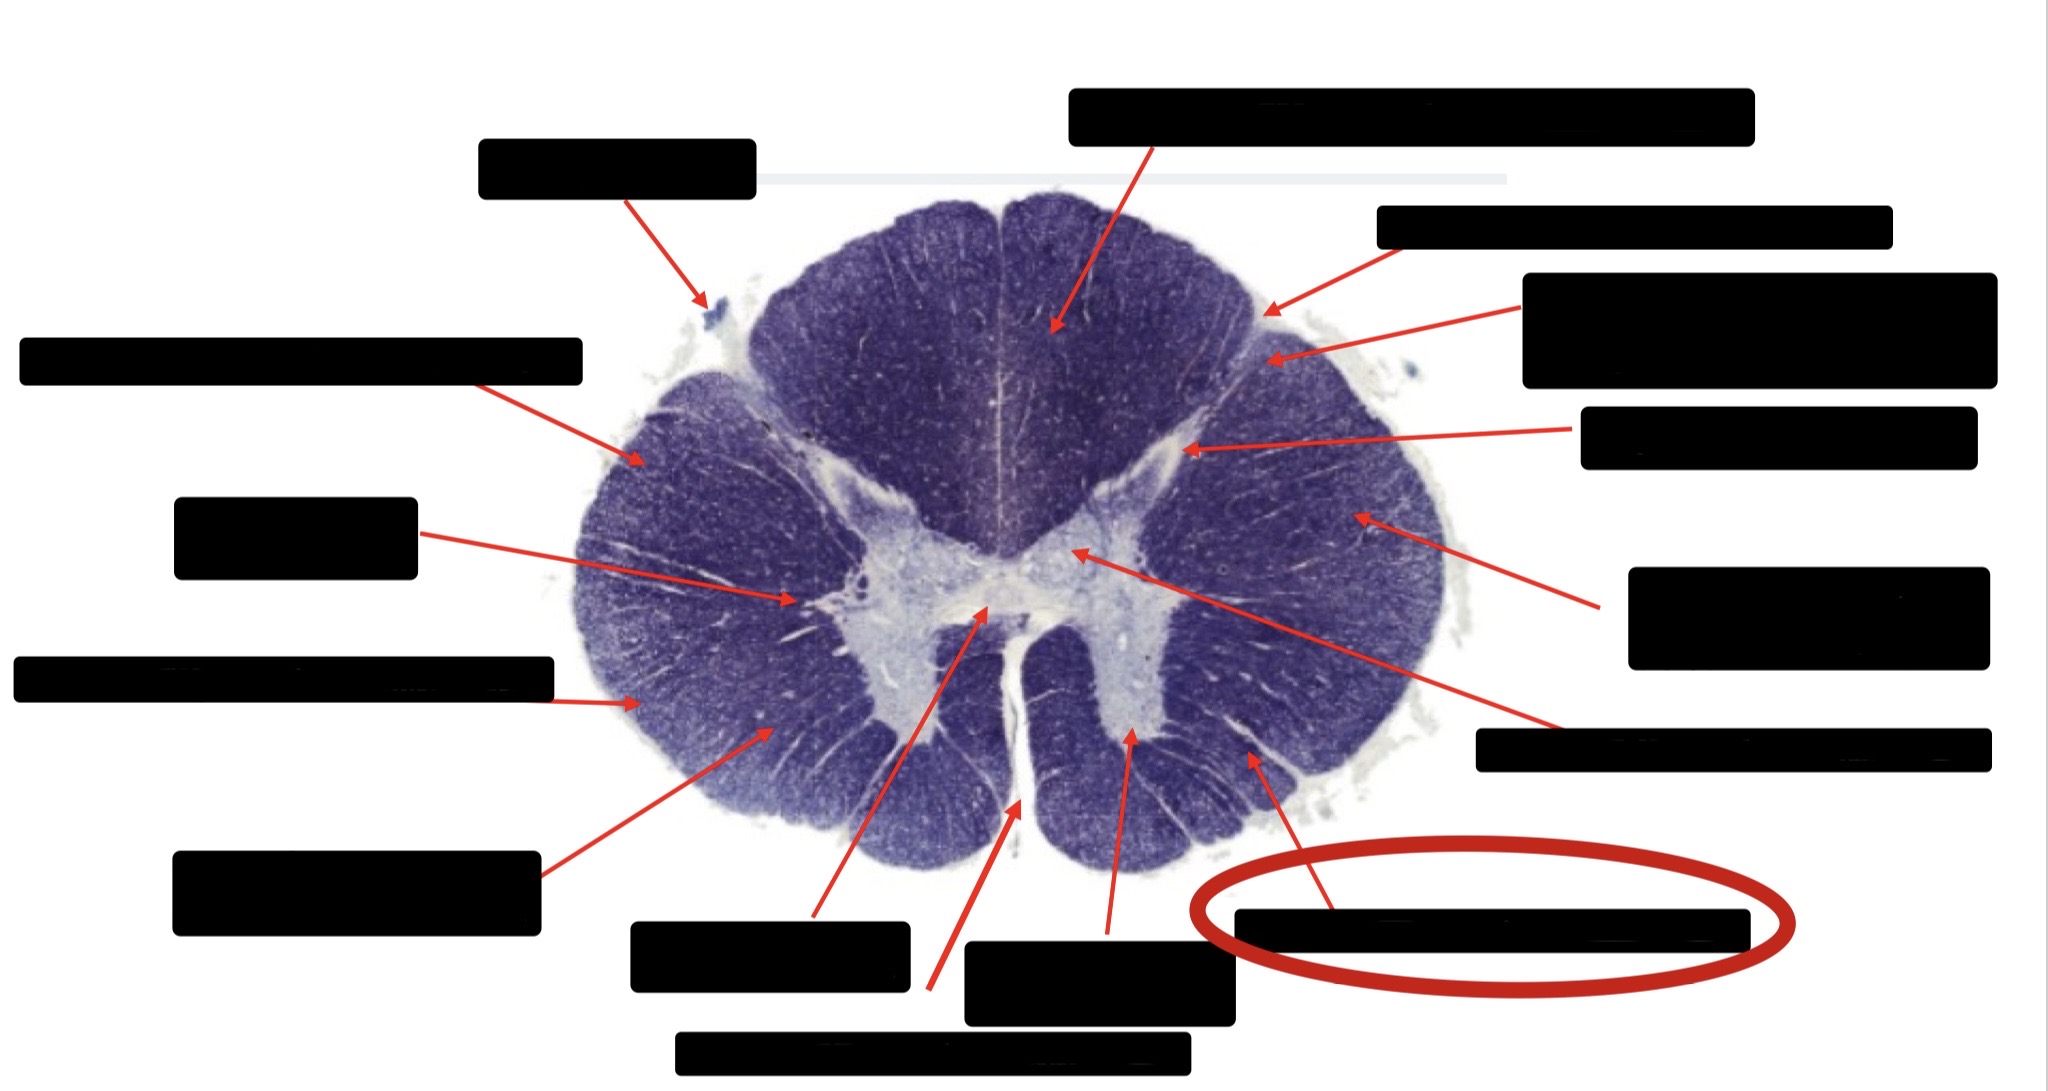

Central Canal

Posterior Column (Fasciculus Gracilis)

Large Fiber Entry Zone

Lissaeur’s Tract & Small Fiber Entry Zone

Substantia Gelatinosa

Lateral Corticospinal Tract

Ventral Root Fibers

Anterior Horn Motor Neurons

Anterior Medial Fissure

Dorsal Rootlet

Posterior Spinocerebellar Tract

Anterior Spinocerebellar Tract

Spinothalmic Tract

Posterior Column (Fasciculus Cuneatus)

Anterior Horn Motor Neurons (Distal Muscles)

Anterior Horn Motor Neurons (Proximal Muscles)

Anterior Corticospinal Tract